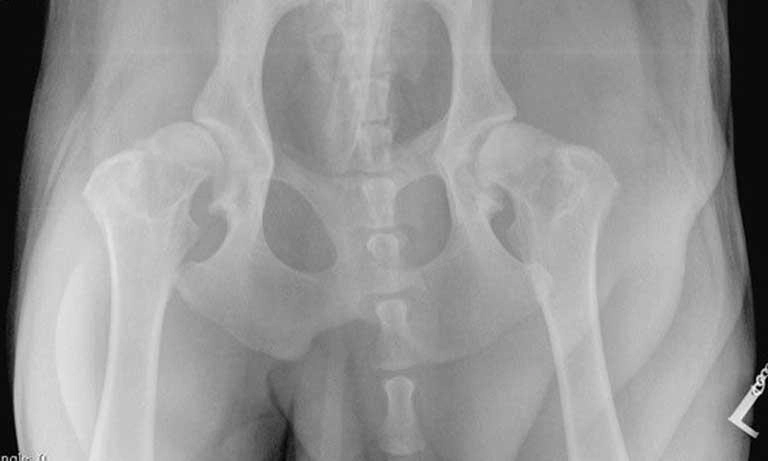

Dijagnoza displazije kukova postavlja se kombinacijom kliničkog pregleda i dijagnostičkih metoda.

Veterinar će procijeniti pokretljivost zgloba, prisutnost boli i opće stanje psa. Konačna potvrda bolesti dobiva se rendgenskim snimanjem, koje jasno pokazuje stupanj promjena na zglobu kuka.